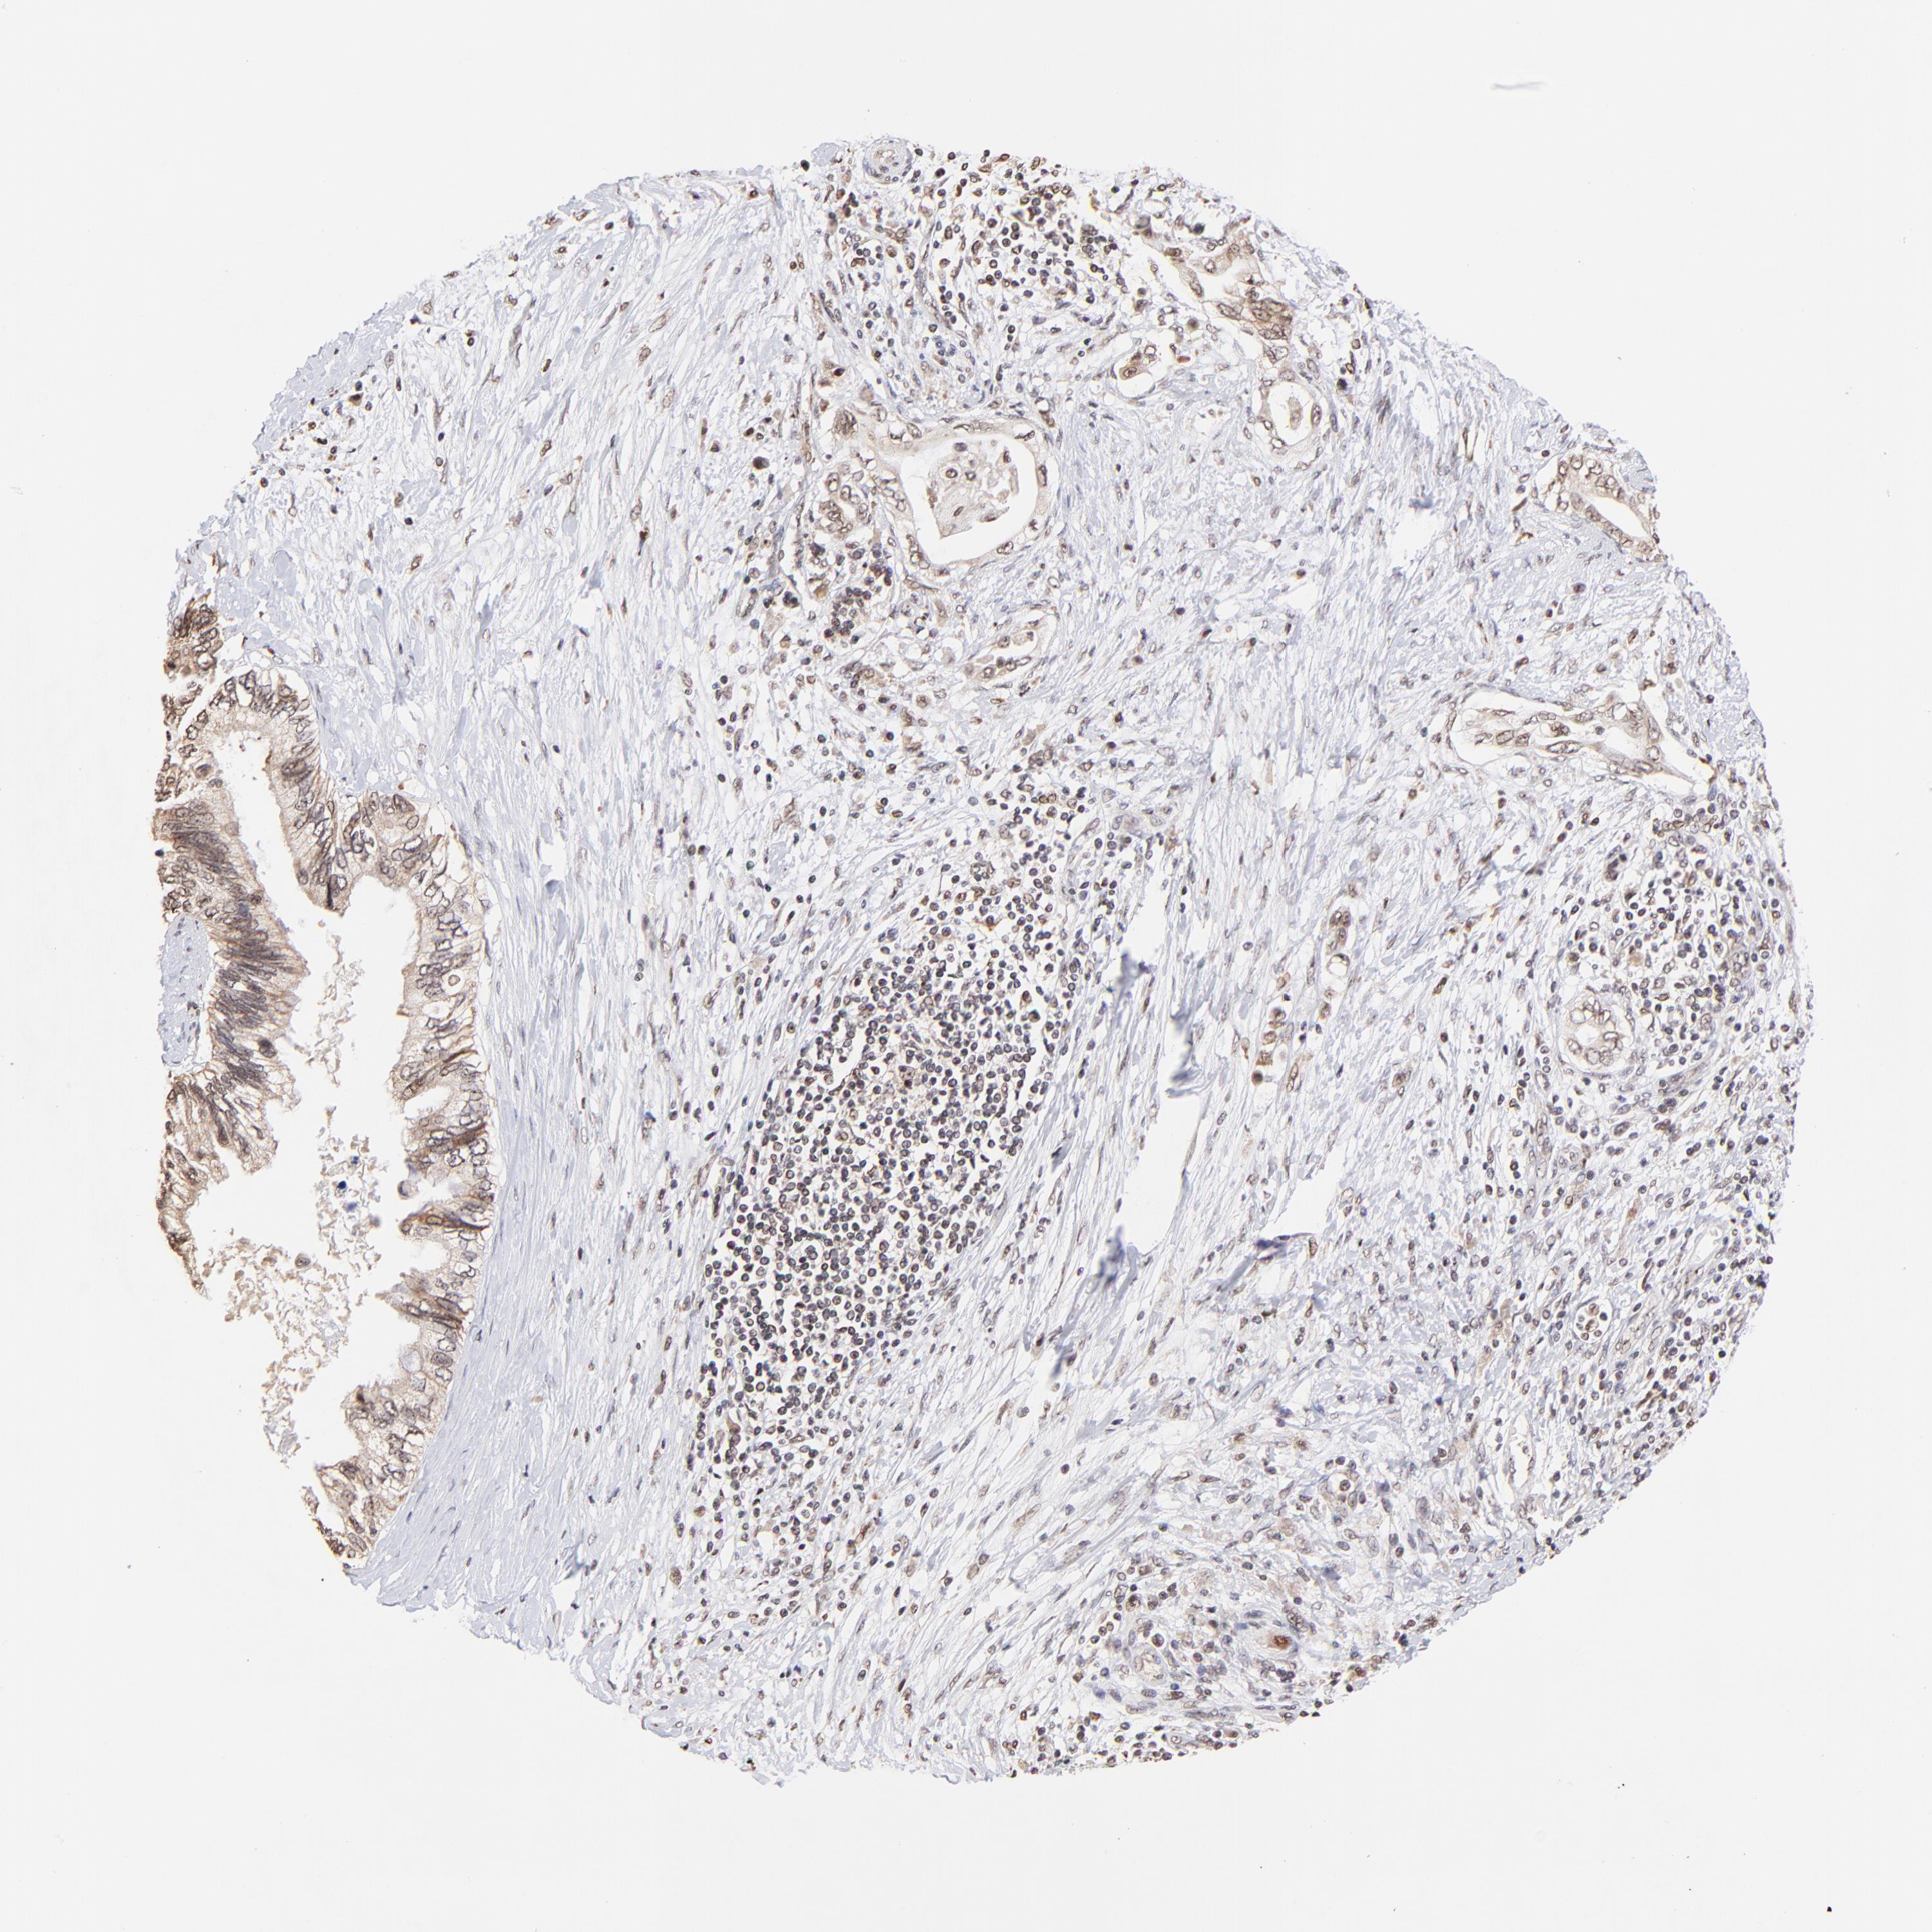

PANCREATIC CANCER - Protein expressioni

A mouse-over function shows sample information and annotation data. Click on an image to view it in a full screen mode. Samples can be filtered based on level of antibody staining by selecting one or several of the following categories: high, medium, low and not detected. The assay and annotation is described here.

Note that samples used for immunohistochemistry by the Human Protein Atlas do not correspond to samples in the TCGA dataset.

Antibody stainingi

Antibody staining in the annotated cell types in the current human tissue is reported as not detected, low, medium, or high, based on conventional immunohistochemistry profiling in selected tissues. This score is based on the combination of the staining intensity and fraction of stained cells.

Each image is clickable and will lead to virtual microscopy that enables deeper exploration of all samples and also displays staining intensity scores, fraction scores and subcellular localization as well as patient and tissue information for each sample.

Antibody HPA003142

Staining

High

Medium

Low

Not detected

Intensity

Strong

Moderate

Weak

Negative

Quantity

>75%

75%-25%

<25%

None

Location

Nuclear

Cytoplasmic/membranous

Cytoplasmic/membranous,nuclear

Adenocarcinoma, NOS